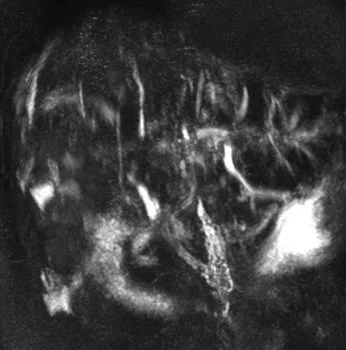

Figure 12.

A. Chez ce patient suivi pour une TIPMP de la tête du pancréas et ne présentant aucun argument clinico-biologique pour une pathologie biliaire, on pourrait discuter de discrètes « irrégularités » des VBIH : aspect en « collier de perles » (tête de flèche), sténose focale (flèche)… En réalité, il ne s’agit que de fausses images, banales en bili-IRM et simplement liées à la résolution spatiale et au rapport signal sur bruit limités : ici les VBIH sont normales.

B. Chez cet autre patient, il existe cette fois-ci des signes objectifs d’atteinte des VBIH : on note de multiples images de « disparition » segmentaire de voies biliaires, associées à une trop bonne visibilité en amont. Il s’agit d’un aspect typique de cholangite sclérosante primitive